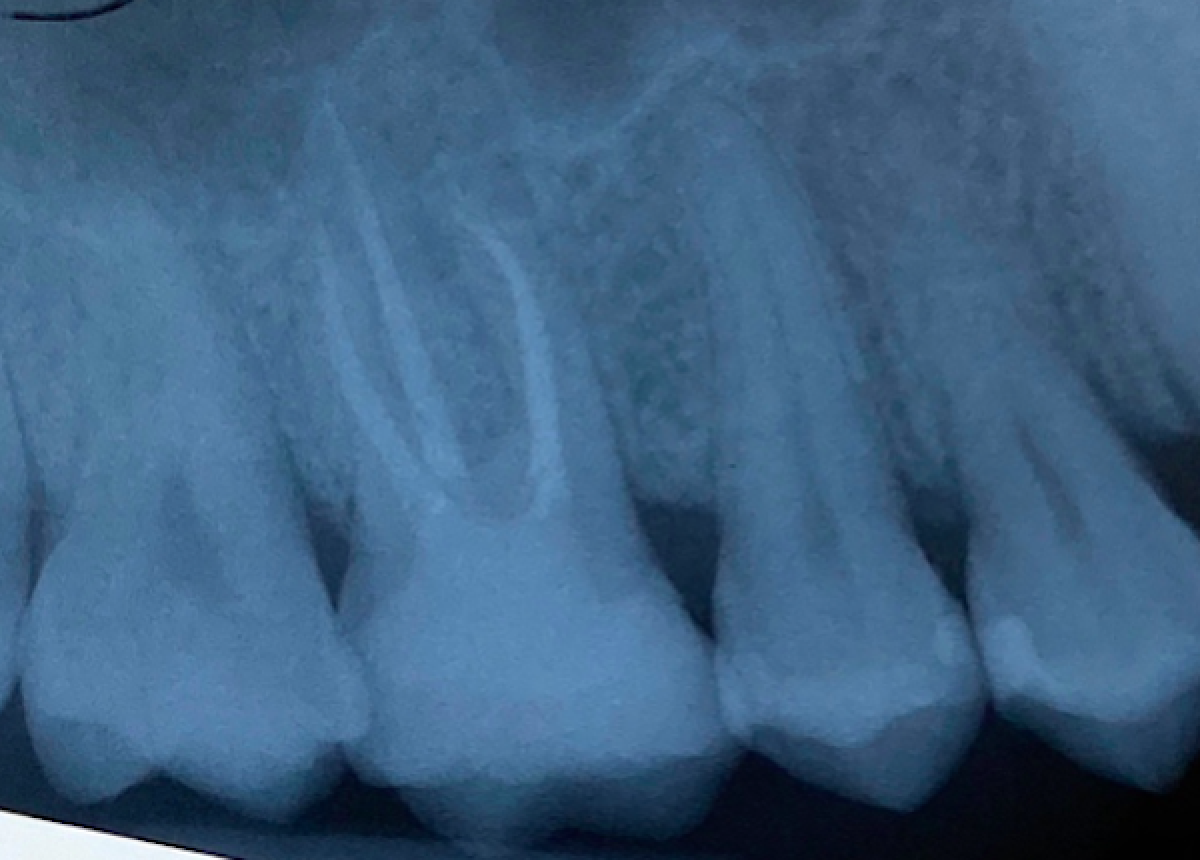

The radiographic examination (fig 2) showed the presence of periapical lesion on 1.6 and an extensive composite filling.